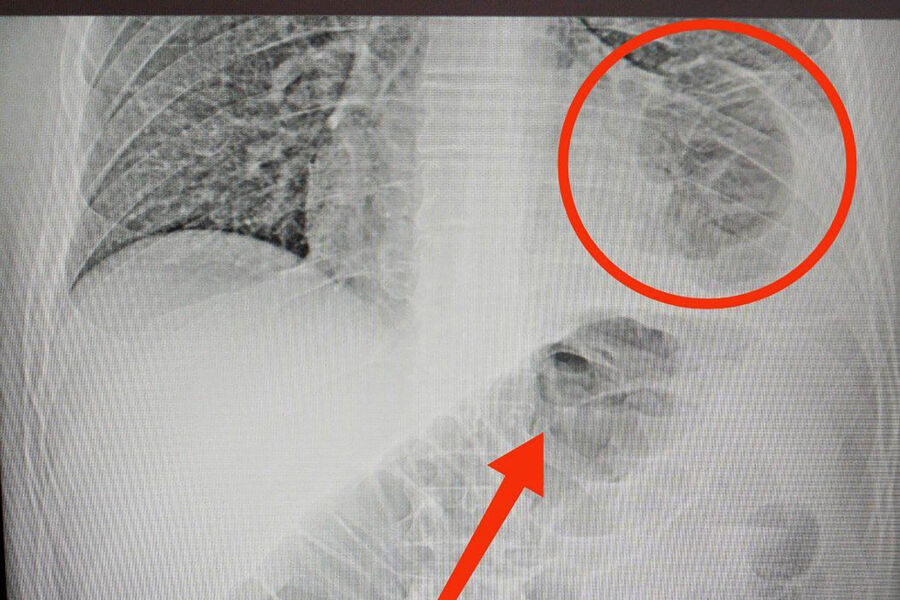

46-летний мужчина обратился в медицинское учреждение с жалобами на боли в животе. В ходе обследования медики обнаружили, что в грудной клетке пациента находится часть кишечника. Оказалось, у мужчины была ущемленная грыжа диафрагмы – редкое состояние, при котором органы брюшной полости через отверстие в диафрагме попадают в грудную клетку.

«Врачи аккуратно извлекли ущемленную кишку из грудной клетки, проверили, нет ли омертвевших участков. После устранили дефект диафрагмы, зашив отверстие», - сообщили в Минздраве.